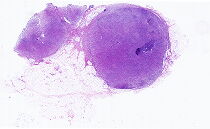

数字切片

男, 27岁, 患者于2025年2月...

男, 65岁, 因“发现背部皮下肿物...

女, 26岁, 既往体健。体检无意中...

男, 36岁, 【主诉】发现纵隔肿物...

男, 34岁, 既往史:否认肝炎史,...

男, 57岁, 主诉:消瘦一年余 现...

男, 73岁, 因“皮疹、白细胞增多...